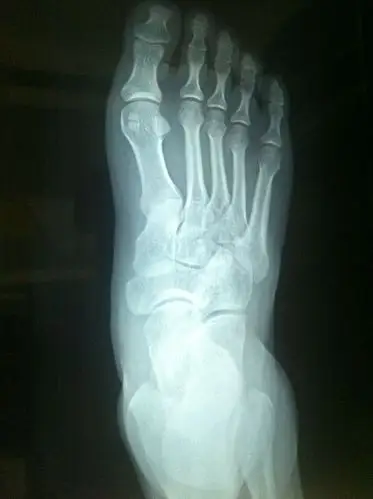

打球崴脚了 麻烦看一下x片

泡 冰敷 没有肿 但是走路完全无法使劲儿 间隔8小时 还是去医院拍片了